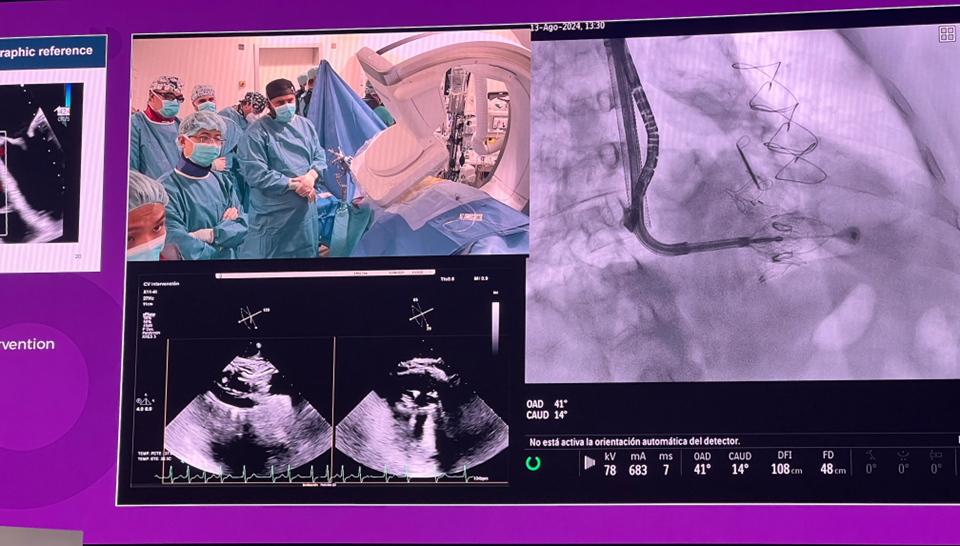

隨后由來自西班牙維哥-阿爾瓦羅昆奎羅醫(yī)院(Hospital Álvaro Cunqueiro, Vigo, Spain)的 Rodrigo Estevez-Loureiro 教授在大會主會場的經(jīng)導管介入瓣膜新技術環(huán)節(jié),帶來了一例 LuX-Valve Plus 手術錄播,對手術植入的步驟和關鍵要點進行了詳細深入的介紹。同時,臺上的多位討論嘉賓也結合他們的 LuX-Valve Plus 手術經(jīng)驗進行了深入的探討。來自香港瑪麗皇后醫(yī)院(Queen Mary Hospital, Hong Kong, China)的 Simon Lam 教授分享了 LuX-Valve Plus 在術前有起搏導線病人中的植入經(jīng)驗,來自巴西圣保羅(Rede D'Or São Luiz, São Paulo, Brazil)的 Vinicius Esteves 教授補充了 LuX-Valve Plus 獨特的非徑向支撐力設計,能夠實現(xiàn)非常低的術后起搏器植入率,來自法國波爾多大學醫(yī)院(CHU de Bordeaux, Bordeaux, France)的 Lionel Leroux 教授則分享了其在LuX-Valve Plus歐洲臨床試驗過程中,對于大尺寸瓣環(huán)植入的優(yōu)異結果。